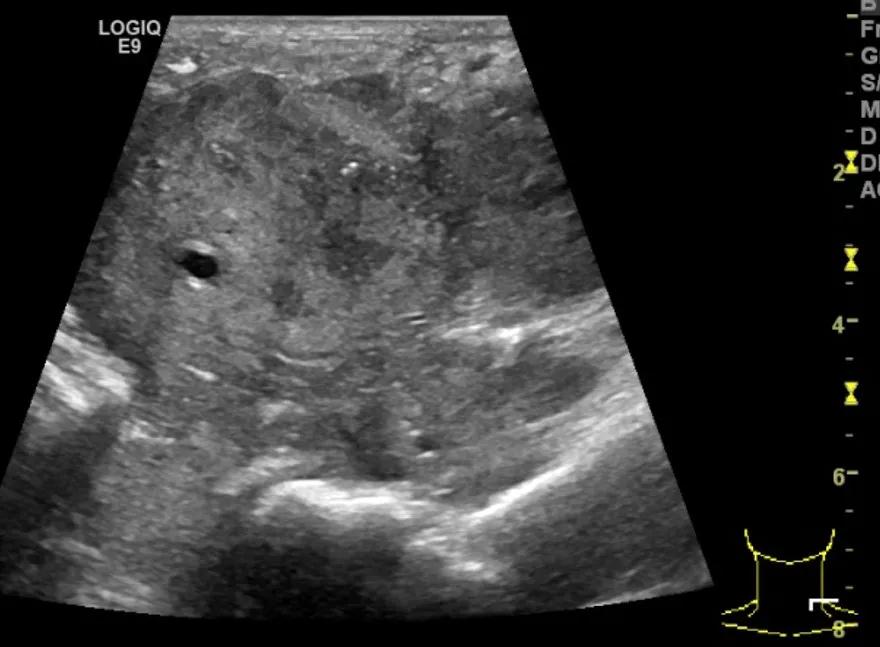

随后,徐栋教授进一步分享了五个临床实战病例,带来了更直观的热消融治疗经验。第一个病例是62岁肺癌患者,术后1年余发现双侧锁骨上淋巴结复发,侵犯神经,存在静脉回流、淋巴回流障碍,肿胀、疼痛非常明显。影像显示患者淋巴结边界不清、形态不规则,存在浸润,血流强化增强。由于患者在系统治疗后进展,且主要目的缓解症状、减瘤。局麻下行热消融术,从后向前逐层消融,热消融之后超声造影即刻评估显示完全充盈缺损,完全覆盖病灶。

(病例1图例)